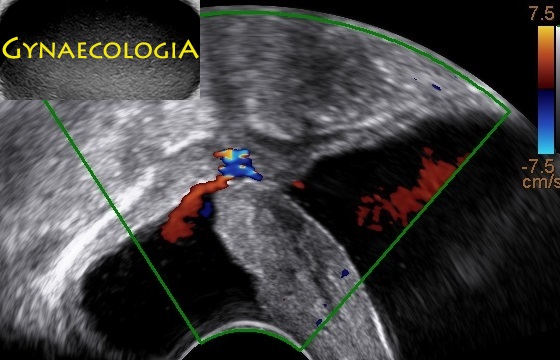

The following images and videos represent an abnormal passageway between the bladder and the vaginal apex following a complicated hysterectomy.